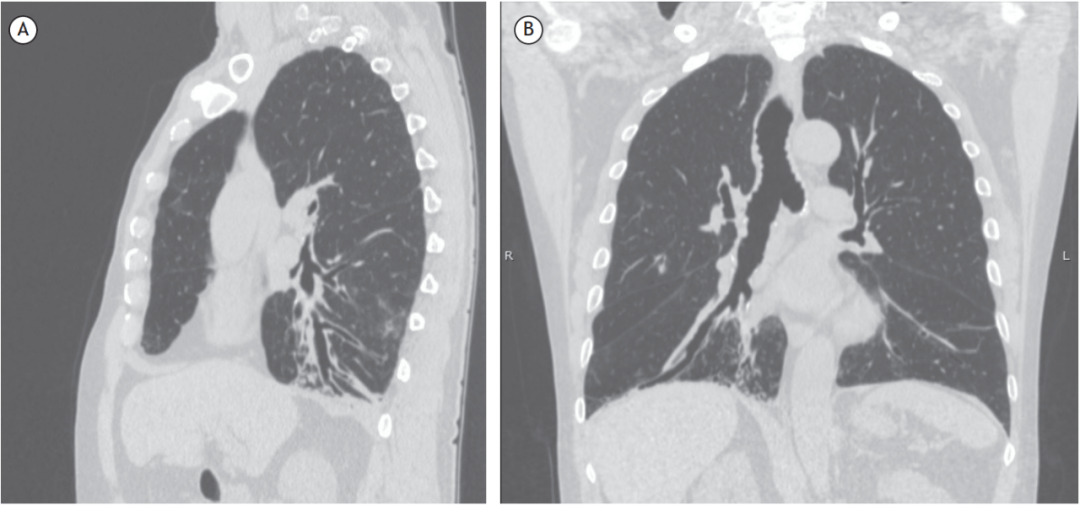

ct矢状面与冠状面图片

a:矢状面ct影像;b:冠状面ct影像;c:矢状面增强ct影像;d:冠状面增强ct

综述吞咽困难致吸入患者的胸部ct表现